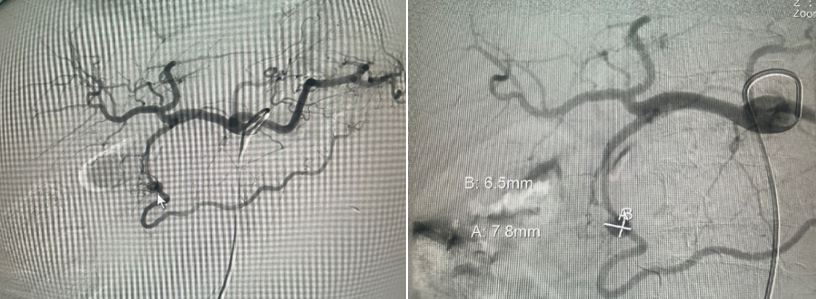

- Đến 8h ngày 27/12:  bệnh nhân lại nôn ra máu tươi, huyết áp dao động 80/40 – 90/50, mạch 120 lần/phút. Bệnh nhân được chỉ định chụp mạch tạng (DSA). Kết quả chụp mạch có 1 túi giả phình nằm ở 1 nhánh của động mạch vị tá tràng đang chảy máu. Bệnh nhân được can thiệp nút túi giả phình này. Sau can thiệp bệnh ổn đinh, theo dõi đên ngày 03/01/2023 bệnh nhân huyết động ổn, không nôn, ăn uống được, xét nghiệm công thức máu ổn. Bệnh nhân được ra viện cùng ngày, sau ra viện ổn.

Hình 7 và 8.  Chụp mạch sau can thiệp